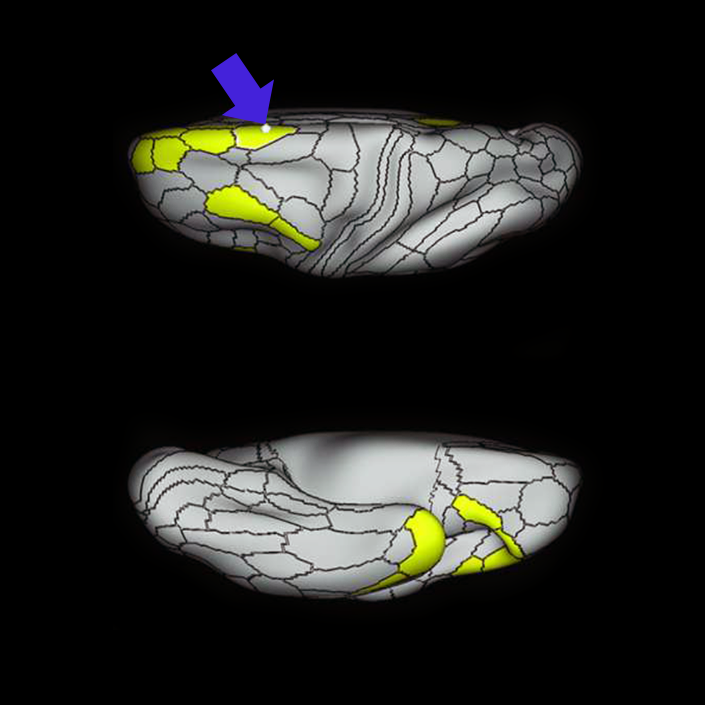

ᐅ SummaryArea 55b: part of the premotor areas. Relatively uncharacterized regions. In 1956, one of the only studies to characterize this regions concluded that the area played a role in language processing. ᐅ Where is it?Area 55b is located on the anterior half of the precental gyrus, approximately half way down its length along the convexity, just inferior to FEF. It also forms the adjacent floor of the precentral sulci and straddles slightly onto the posterior edge of the middle frontal gyrus. ᐅ What are its borders?Area 55b borders area FEF superiorly and PEF and area 6v inferiorly. Area 4 is its posterior border and areas 8AV and 8C form its anterior border across the precentral sulcus. ᐅ What are its functional connections?Area 55b demonstrates functional connectivity to area 4 in the motor strip, areas SCEF and SFL in the premotor areas, areas IFSp, IFJa, 8AV, 44, 45, and 47L in the lateral frontal lobe, areas STSda and STSdp in the temporal lobe, areas PSL and STV in the posterior opercular cortices, and area TPOJ1 in the lateral occipital lobe. ᐅ What are its white matter connections?Area 55b is structurally connected to the contralateral hemisphere and the superior longitudinal fasciculus. Contralateral connections course through the body of the corpus callosum to 6ma, 6a and 6mp. Connections with the superior longitudinal fasciculus connect 55b to parcellations PHT and PFm, and this tract terminates eventually in the temporal lobe at TGd. Local short association fibers connect with 8Av, 8C, IFJp, 3a, 3b and PEF. ᐅ What is known about its function?Area 55b is a relatively uncharacterized region. In 1956, one of the only studies to characterize this region concluded that the area played a role in language processing. |

A: lateral-medial

B: anterior-posterior

C: superior-inferior

DTI image |